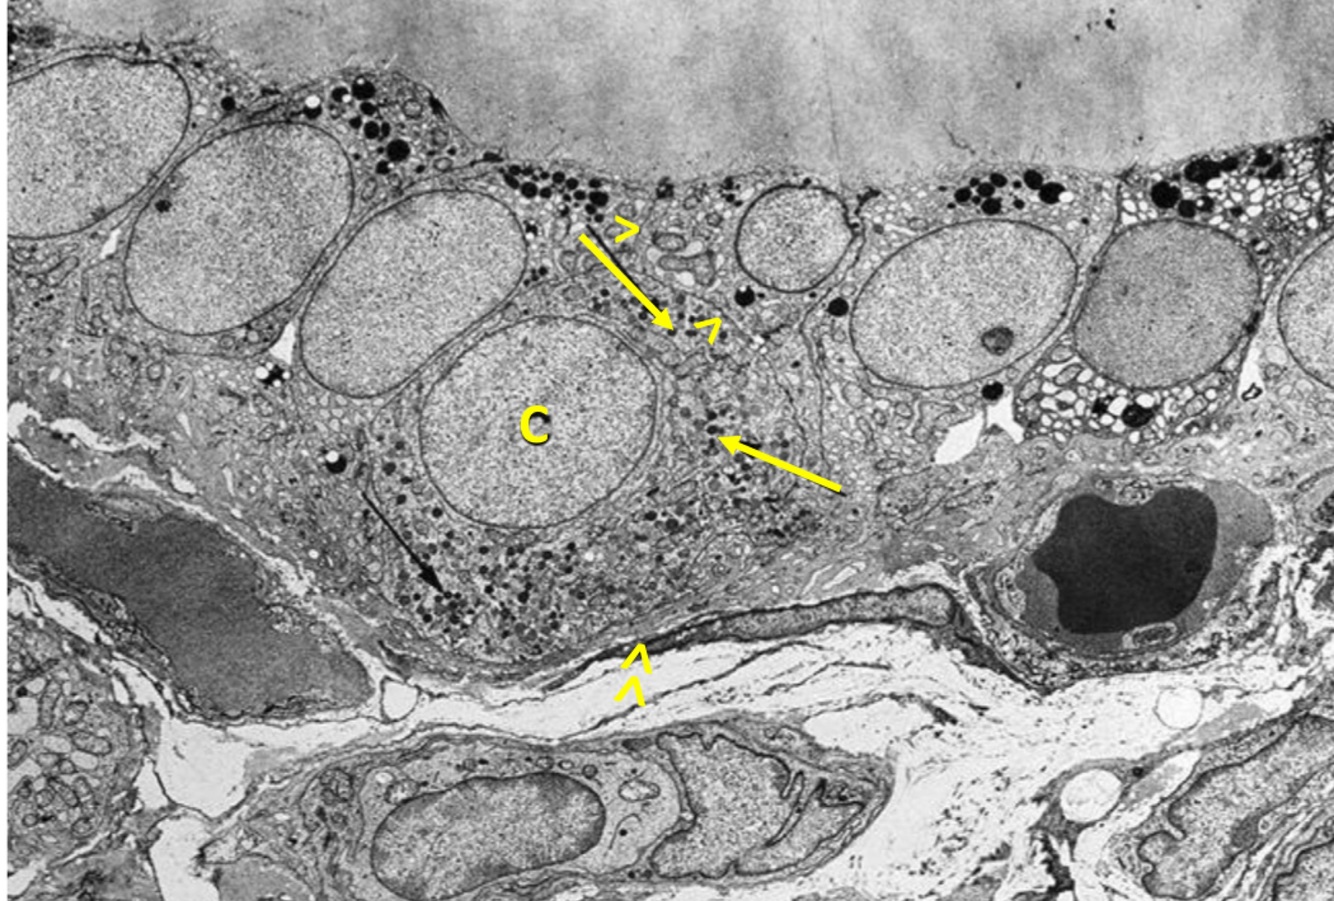

Figure illustrates 4 histological variations of Thyroid follicele appearance , define each one

histological picture of Embryonal adenoma ?

closely packed cells forming cords or trabeculae

histological picture of Fetal adenoma ?

small follicles containing no or little colloid separated by abundant loose connective tissue

histological picture of Simple adenoma ?

shows closely packed follicles of normal size

histological picture of Colloid adenoma ?

large follicles filled with colloid and lined by flat epithelium

histological picture of Hürthle cell adenoma ?

shows large granular cells with abundant eosinophilic cytoplasm arranged in trabecular pattern